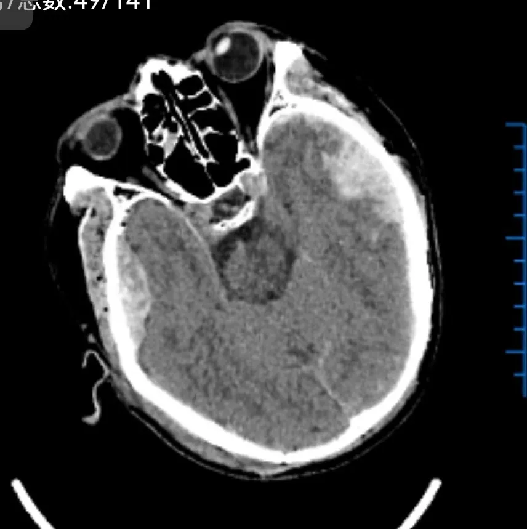

术前: